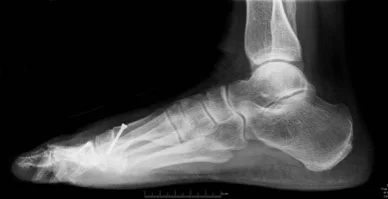

Ankle Bostrum Ligament Repair

Brostrum ligament repair with internal brace, to reduce pain and instability of the ankle joint and prevent long-term arthritis to the ankle joint. Read more >>